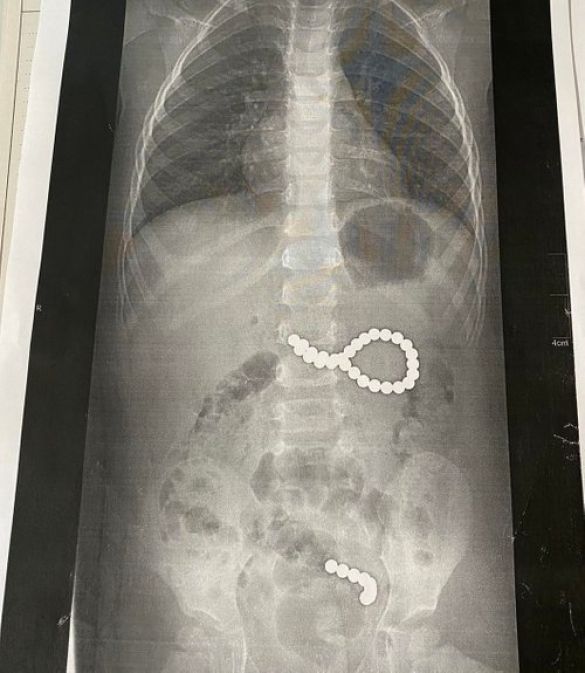

Дев’ять кульок під дією магнітного поля утворили ланцюжок і потрапили в кишківник, ще 27 кульок утворили неправильне коло і потрапити в кишківник не могли. Дівчинку довелося терміново оперувати.

“Дев’ять кульок, які дитина проковтнула у п’ятницю, утворили ланцюжок, бо було сильне магнітне поле. І вони пройшли зі шлунка в тонкий кишківник. А ті 27 магнітних кульок, які дитина проковтнула у суботу, утворили неправильне коло і їх терміново треба було діставати. Кульки були діаметрои 4 мм, найвірогідніше, з якогось конструктора”, – каже Оксана Горбач.